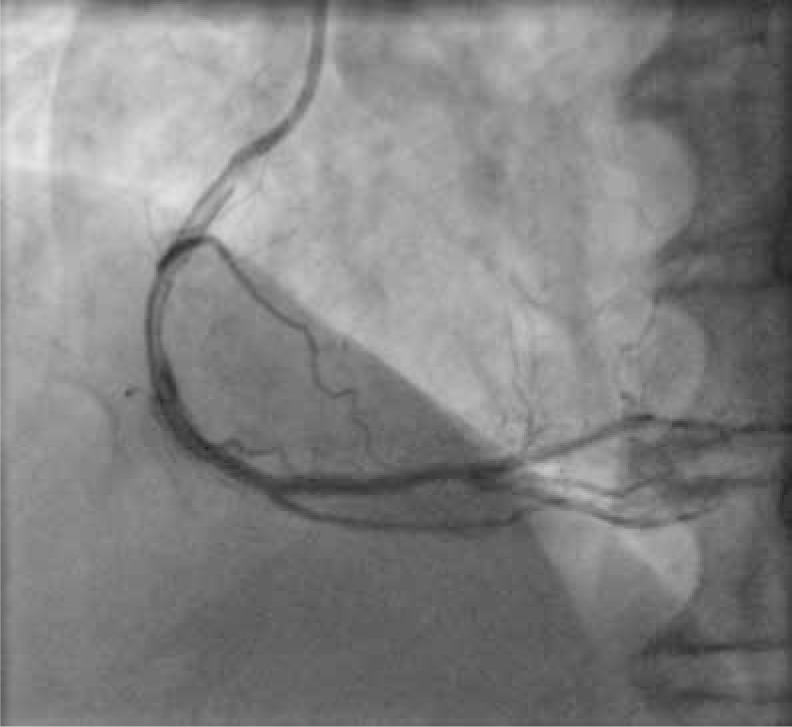

Dissection after predilatation, before BVS implantation, occurred in 22 patients, and in 17 of them it was covered by BVS implantation with optimal angiographic results. Five of them were finally in the dissection group. In another 4 patients from the dissection group, dissection appeared after BVS implantation and required additional intervention, but it was absent after predilatation. The description of dissection according to the NHLBI classification [2] is presented in Table I. Examples of angiographic images of individual dissection classes are shown in Table II.

Table II

Coronary artery dissection – classification